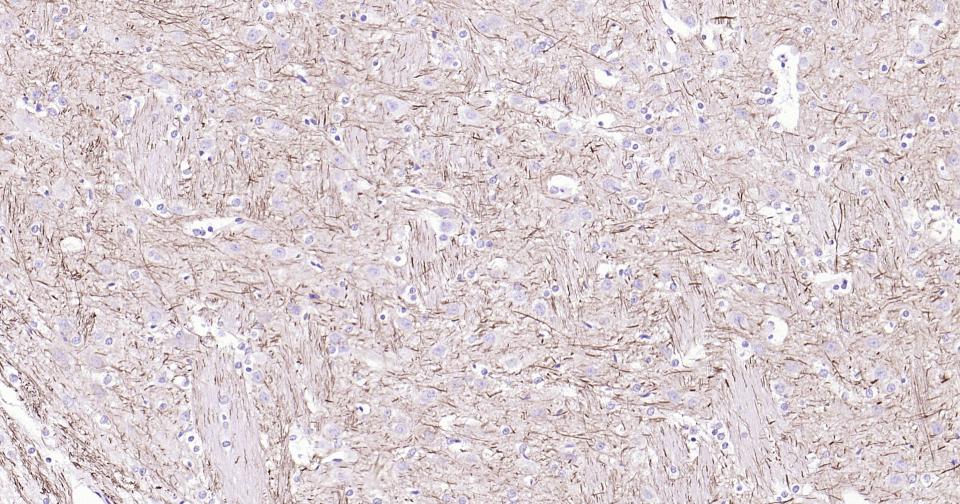

Paraformaldehyde-fixed, paraffin embedded Human Cerebrum; Antigen retrieval by boiling in sodium citrate buffer (pH6.0) for 15 min; Antibody incubation with NEFH Monoclonal Antibody, Unconjugated(bsm-60885R) at 1:200 overnight at 4°C, followed by conjugation to the SP Kit (Rabbit, SP-0023) and DAB (C-0010) staining.